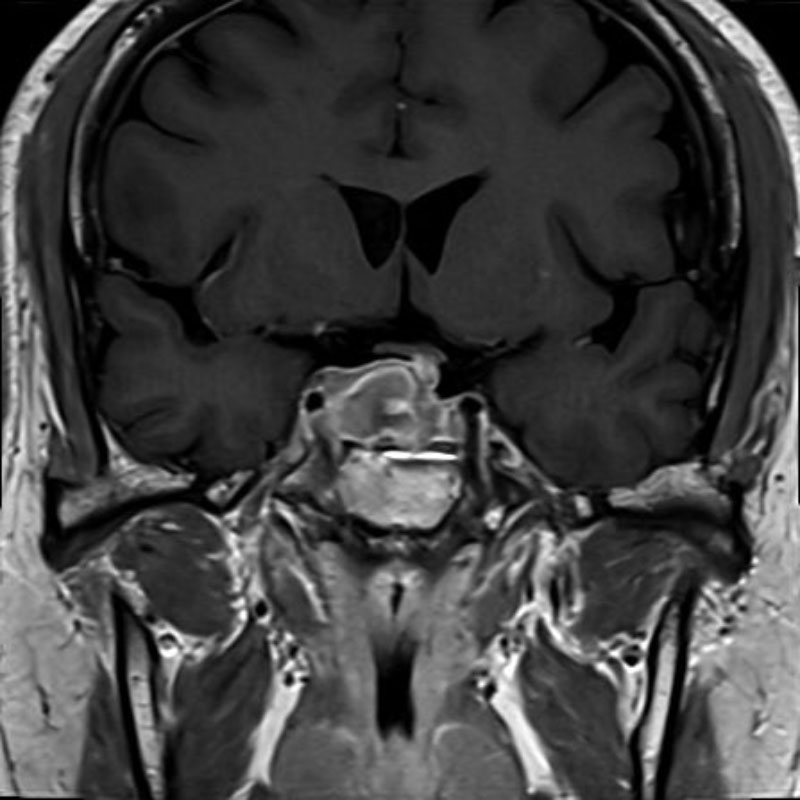

頭蓋内腫瘍摘出術

No.’25_103 手術前1

No.’25_103 手術前2